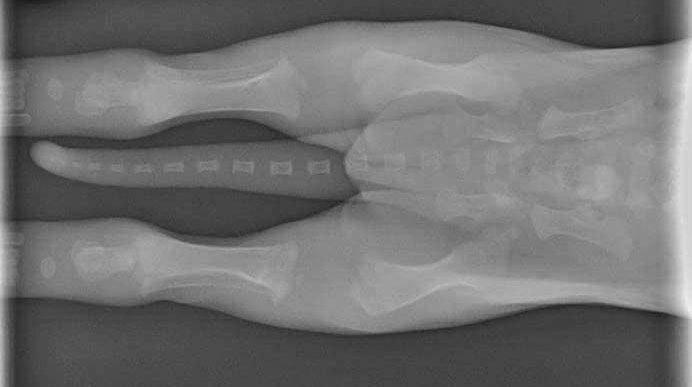

Krallen

windspiel-krallenschneider